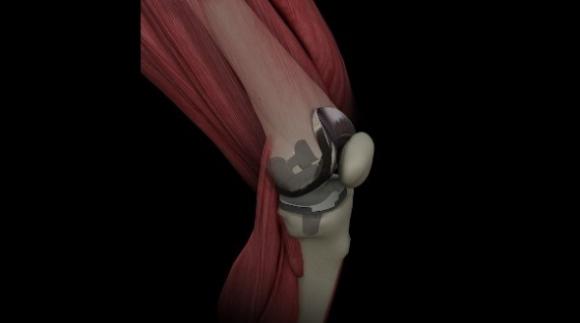

Desarrollan en Argentina una innovadora prótesis de revisión para reemplazo total de rodilla

Foto: Ezequiel Kobrinsky Una innovadora prótesis de revisión para reemplazo total de rodilla con diseño anatómico no simétrico fue desarrollada en Argentina. La misma puede adaptarse en forma óptima tanto a la...